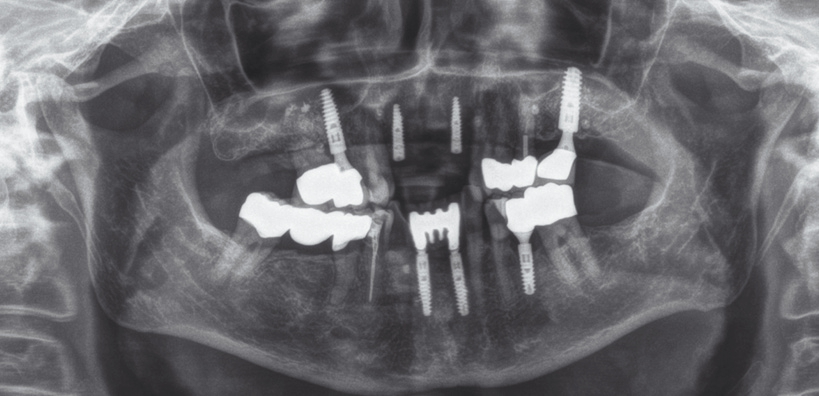

50 Jahre alte Patientin, Nicht-Raucherin ohne größere Risikofaktoren. Die radiologischen Aufnahmen zeigten insuffiziente Versorgung der maxillaren Frontzähne (11, 12, 21 und 22) mit Lockerungsgrad 3 und Knochenabbau bis in das obere Wurzeldrittel (Abb. 1).

Das post-operative Follow-up zeigte eine komplikationslose Heilung. Sechs Monate nach der Operation wurde das Re-entry durchgeführt und Gingiva-Former eingesetzt (Abb. 19). Die provisorische Brücke zeigte ästhetische Ergebnisse bereits sechs Monate nach Operation (Abb. 20). Das Röntgenbild zeigte stabile Knochenverhältnisse (Abb. 21).